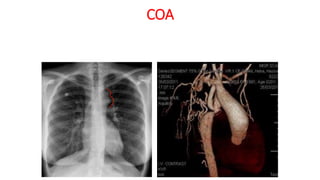

COA

Two classic radiologic signs associated with aortic coarctation are

the figure-of-three sign and the reverse figure-of-three sign. The

aortic segment affected by coarctation has a shape that resembles

the number 3 on frontal chest radiographs. The reverse figure-of-

three sign, a mirror image of the number 3, is observed on the left

anterior oblique view during barium esophagography. This sign is

seen in 50%–66% of adults with aortic coarctation

COARCTATION OF AORTA

• Radiographic features:

• Aortic figure 3

• Reverse figure 3 of Barium

filled esophagus

• Inferior rib notching (3rd to 8th,

>8 yrs, dt dilated intercostal

arteries)

• LV hypertrophy

figure 3 sign

Aortic Caliber change local narrowing turbulent flow

3 figure sign due to pre and post dilatation, reverse 3 sign , dilatation of arch